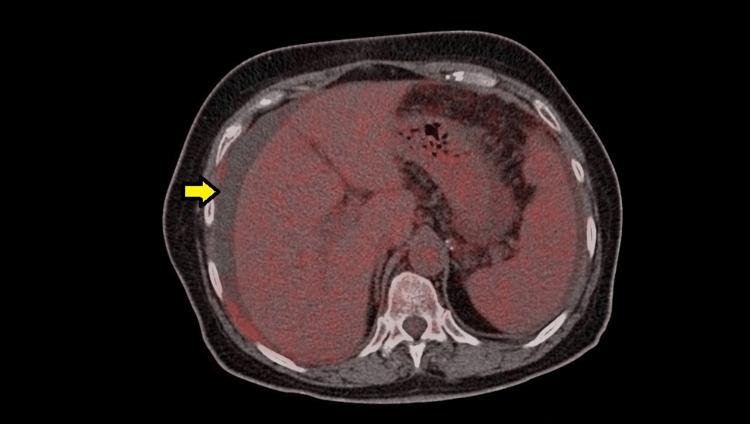

Peritoneal tuberculosis (TB) is a rare disease among the general population that can be seen in patients with associated immunocompromised conditions such as diabetes mellitus, human immunodeficiency virus (HIV)-positive patients, patients with liver cirrhosis, patients on peritoneal dialysis, and patients on treatment with anti-tumor necrosis factor (TNF) agents. Patients who already have active pulmonary TB and who are not treated promptly can develop disseminated disease within the lungs or can affect extrapulmonary organ systems such as the nervous system, gastrointestinal system, or urinary system. It is unusual to see an otherwise healthy person develop peritoneal TB as a first-time diagnosis, without any previous exposure to TB or any immunocompromising condition. The diagnosis of this condition can be tricky as the clinical and radiological manifestations of this disease strongly mimic that of malignancy, such as ovarian cancer or peritoneal carcinomatosis. In the majority of cases, the first impression of malignancy is made while examining the radiological images of the abdomen, and only after obtaining the biopsy results, an unexpected diagnosis of peritoneal TB is established. Hence, it is an interesting and uncommon diagnosis, which should always be kept in mind while managing patients with an apparent gynecological malignancy. Here, we report a case of a 65-year-old female patient who presented with a history of abdominal pain and weight loss. Initial investigation with abdominal ultrasonography revealed ascites with multiple sub-centimeter mesenteric lymphadenopathies. She also had an elevated cancer antigen 125 (CA-125), which further raised suspicion of gynecological malignancy. However, following the investigations, it was found that the actual diagnosis was an unexpected one.

腹膜结核在普通人群中是一种罕见疾病,可见于患有相关免疫功能低下疾病的患者,如糖尿病患者、人类免疫缺陷病毒(HIV)阳性患者、肝硬化患者、腹膜透析患者以及接受抗肿瘤坏死因子(TNF)药物治疗的患者。已经患有活动性肺结核且未及时治疗的患者,肺部可能会发展为播散性疾病,或者可能影响肺外器官系统,如神经系统、胃肠道系统或泌尿系统。在没有任何既往结核接触史或任何免疫功能低下情况的情况下,一个原本健康的人首次被诊断为腹膜结核是不常见的。这种疾病的诊断可能很棘手,因为其临床和影像学表现与恶性肿瘤(如卵巢癌或腹膜转移癌)极为相似。在大多数情况下,在检查腹部影像学图像时首先会怀疑是恶性肿瘤,只有在获得活检结果后,才会意外确诊为腹膜结核。因此,这是一个有趣且不常见的诊断,在处理疑似妇科恶性肿瘤的患者时应始终牢记。在此,我们报告一例65岁女性患者,她有腹痛和体重减轻的病史。腹部超声初步检查显示有腹水,伴有多个直径小于1厘米的肠系膜淋巴结肿大。她的癌抗原125(CA - 125)也升高,这进一步增加了对妇科恶性肿瘤的怀疑。然而,经过进一步检查,发现实际诊断出人意料。